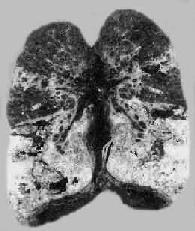

图18-8 慢性纤维空洞型肺结核病(冠状切面) 右上叶,左上叶上部和左下叶上部都有厚壁空洞形成;肺门淋巴结无结核病变 临床上,病程常历时多年,时好时坏。症状的有无与病变的好转或恶化相关。由于空洞与支气管相通,成为结核病的传染源,故此型有开放性肺结核之称。如空洞壁的干酪样坏死侵蚀较大血管,可引起大咯血,严重者可危及生命,病人多因吸入大量血液而窒息死亡。如空洞穿破胸膜可引起气胸或脓气胸。经常排出含菌痰液可引起喉结核。咽下含菌痰液可引起肠结核。肺广泛纤维化还可导致肺动脉高压,引起肺源性心脏病。 较小的结核空洞经过适当治疗可发生瘢痕愈合。较大的空洞经治疗后,洞壁坏死物质脱落净化,洞壁结核性肉芽组织逐渐转变为纤维瘢痕组织,与空洞邻接的支气管上皮增生并向空洞内伸延,覆盖于空洞内面。此时空洞虽仍存在,但已属愈合。空洞的这种愈合方式称为开发性愈合。 4.干酪样肺炎此种肺炎发生在机体免疫力极低,对结核菌的变态反应过高之病人,可由浸润型肺结核恶化进展而来,或由急、慢性空洞内的细菌经支气管播散所致。按病变范围大小的不同而分为小叶性和大叶性干酪样肺炎。后者可累及一个肺叶或几个肺叶。肉眼观,肺叶肿大变实,切面呈黄色干酪样,坏死物质液化排出后可见有急性空洞形成(图18-9)。镜下,肺泡腔内有大量浆液纤维素性渗出物,内含主为巨噬细胞的炎性细胞,且见广泛的干酪样坏死。抗酸染色可查见大量结核菌。此型结核病情危重,目前已很少见。

图18-7 肺粟粒性结核病 图中白色点状病灶为粟粒性结核灶 慢性粟粒性肺结核病多见于成年人,这时肺原发综合征业已钙化痊愈,结核杆菌由肺外(骨关节、泌尿生殖道及肾上腺等处)结核病灶较长期、间歇性地进入血流,播散于肺内,形成新旧不等的病变。间隔时间可为数月甚至数年。患者多因结核性脑膜炎死亡。 3)肺外器官结核病:或称肺外结核病,大多是原发性肺结核病经血道播散的后果。在原发综合征期间如有少量结核杆菌经原发灶内的毛细血管侵入血流,则能在肺外某些器官(骨关节,泌尿生殖器官、神经系统、浆膜、皮肤等)内形成个别的结核病灶。这些病灶可自愈或潜伏下来,经过较长时间后,当机体抵抗力下降时乃恶化进展为肺外器官结核病。 (二)继发性肺结核病 继发性肺结核病(secondary pulmonary tuberculosis)是指再次感染结核菌所引起的肺结核病,多见于成年人,故又称成人型肺结核病。肺内的病变常开始于肺尖,称再感染灶。关于再感染灶的形成机制有以下两种学说:①外源性再感染学说,认为继发性肺结核的发病是由外界重新感染所致,与原发性肺结核无任何联系;②内源性再感染学说,认为继发性肺结核病的再感染灶大多是由原发性肺结核病血源性播散时在肺尖部形成的病灶。在机体免疫力下降时,潜伏的病灶可发展为继发性肺结核病。此外,也可是肺内未愈合的原发灶内的结核菌经小支气管蔓延或由肺外器官结核病灶内的结核菌经血道播散至肺的结果。 继发性肺结核病患者对结核杆菌已有一定的免疫力或过敏性,所以继发性肺结核病与原发性肺结核病的病变有以下不同特点:①病变多从肺尖开始,这可能与人体直立位时该处动脉压低、血循环较差,随血流带去的巨噬细胞较少,加之通气不畅,以致局部组织抵抗力较低,细菌易在该处繁殖有关。②由于变态反应,病变发生迅速而且剧烈,易发生干酪样坏死,同时由于免疫反应较强,在坏死灶周围每有以增生为主的病变,形成结核结节。免疫反应不仅能使病变局限化,而且还可抑制细菌的繁殖,防止细菌沿淋巴道和血道播散,因此肺门淋巴结一般无明显病变,由血源播散而引起全身粟粒性结核病者亦极少见。病变在肺内蔓延主要通过受累的支气管播散。③病程较长,随着机体免疫反应和变态反应的消长,临床经过常呈波浪起伏状,时好时坏,病变有时以增生性变化为主,有时则以渗出、坏死变化为主,常为新旧病变交杂。 因此,继发性肺结核病的病变和临床表现都比较复杂。根据其病变特点和临床经过可分为以下几种主要类型: 1.局灶型肺结核 病变多位于肺尖下2~4cm处,右肺较多。病灶可为一个或数个,一般约0.5~1cm大小,多数以增生性病变为主,也可为渗出性病变,中央发生干酪样坏死。如病人免疫力较强,病灶常发生纤维化、钙化而痊愈。临床上病人常无明显自觉症状,多在体检时发现,属无活动性肺结核一类。如病人免疫力降低时,可发展成为浸润型肺结核。 2.浸润型肺结核是临床上最常见的一种类型,属于活动性肺结核。大多是局灶型肺结核发展的结果,少数也可一开始即为浸润型肺结核。病变中央常有较小的干酪样坏死区,周围有广阔的病灶周围炎包绕。镜下,肺泡内充满浆液、单核细胞、淋巴细胞和少数中性粒细胞,病灶中央常发生干酪样坏死。病人常有低热、盗汗、食欲不振、全身无力等中毒症状和咳嗽、咯血等。痰中常可查出结核杆菌。如能早期适当治疗,一般多在半年左右可完全吸收或部分吸收,部分变为增生性病变,最后,可通过纤维化、包裹和钙化而痊愈。 如病人免疫力差或未及时得到适当治疗,病变可继续发展,干酪样坏死灶扩大(浸润进展期)。坏死物质液化经支气管排出后形成急性空洞,洞壁粗糙不整,内壁坏死层中有大量结核杆菌,坏死层外可有薄层结核性肉芽组织包绕。从空洞中不断向外排出含菌的液化坏死物质,可经支气管播散,引起干酪样肺炎(溶解播散)。如靠近肺膜的空洞穿破肺膜,可造成自发性气胸;如果大量液化坏死物质进入胸腔,可发生结核性脓气胸。急性空洞一般较易愈合,如能给以及时和强有力的抗结核治疗,这种空洞可通过洞壁肉芽组织增生而逐渐缩小,最终形成瘢痕而治愈,或通过空洞塌陷,形成索状瘢痕愈合。若急性空洞经久不愈,则可发展为慢性纤维空洞型肺结核。 3.慢性纤维空洞型肺结核为成人慢性肺结核的常见类型,多在浸润型肺结核形成急性空洞的基础上发展而来。病变特点是在肺内有一个或多个厚壁空洞形成。同时在同侧肺组织,有时也可在对侧肺组织,特别是肺下叶可见由支气管播散引起的很多新旧不一、大小不等、病变类型不同的病灶,部位愈下病变愈新鲜。空洞多位于肺上叶,大小不一,呈不规则形,洞壁厚,有时可达1cm以上。洞内常见残存的梁柱状组织,多为有血栓形成并已机化闭塞的血管。空洞附近肺组织有显著纤维组织增生和肺膜增厚(图18-8)。镜下,洞壁分三层:内层为干酪样坏死物质,其中有大量结核杆菌;中层为结核性肉芽组织;外层为增生的纤维组织。由于病情迁延,病变广泛,新旧不等,肺组织遭到严重破坏,可导致肺组织的广泛纤维化,最终演变为硬化型肺结核,使肺体积缩小、变形、变硬、肺膜广泛增厚并与胸壁粘连,可严重影响肺功能。